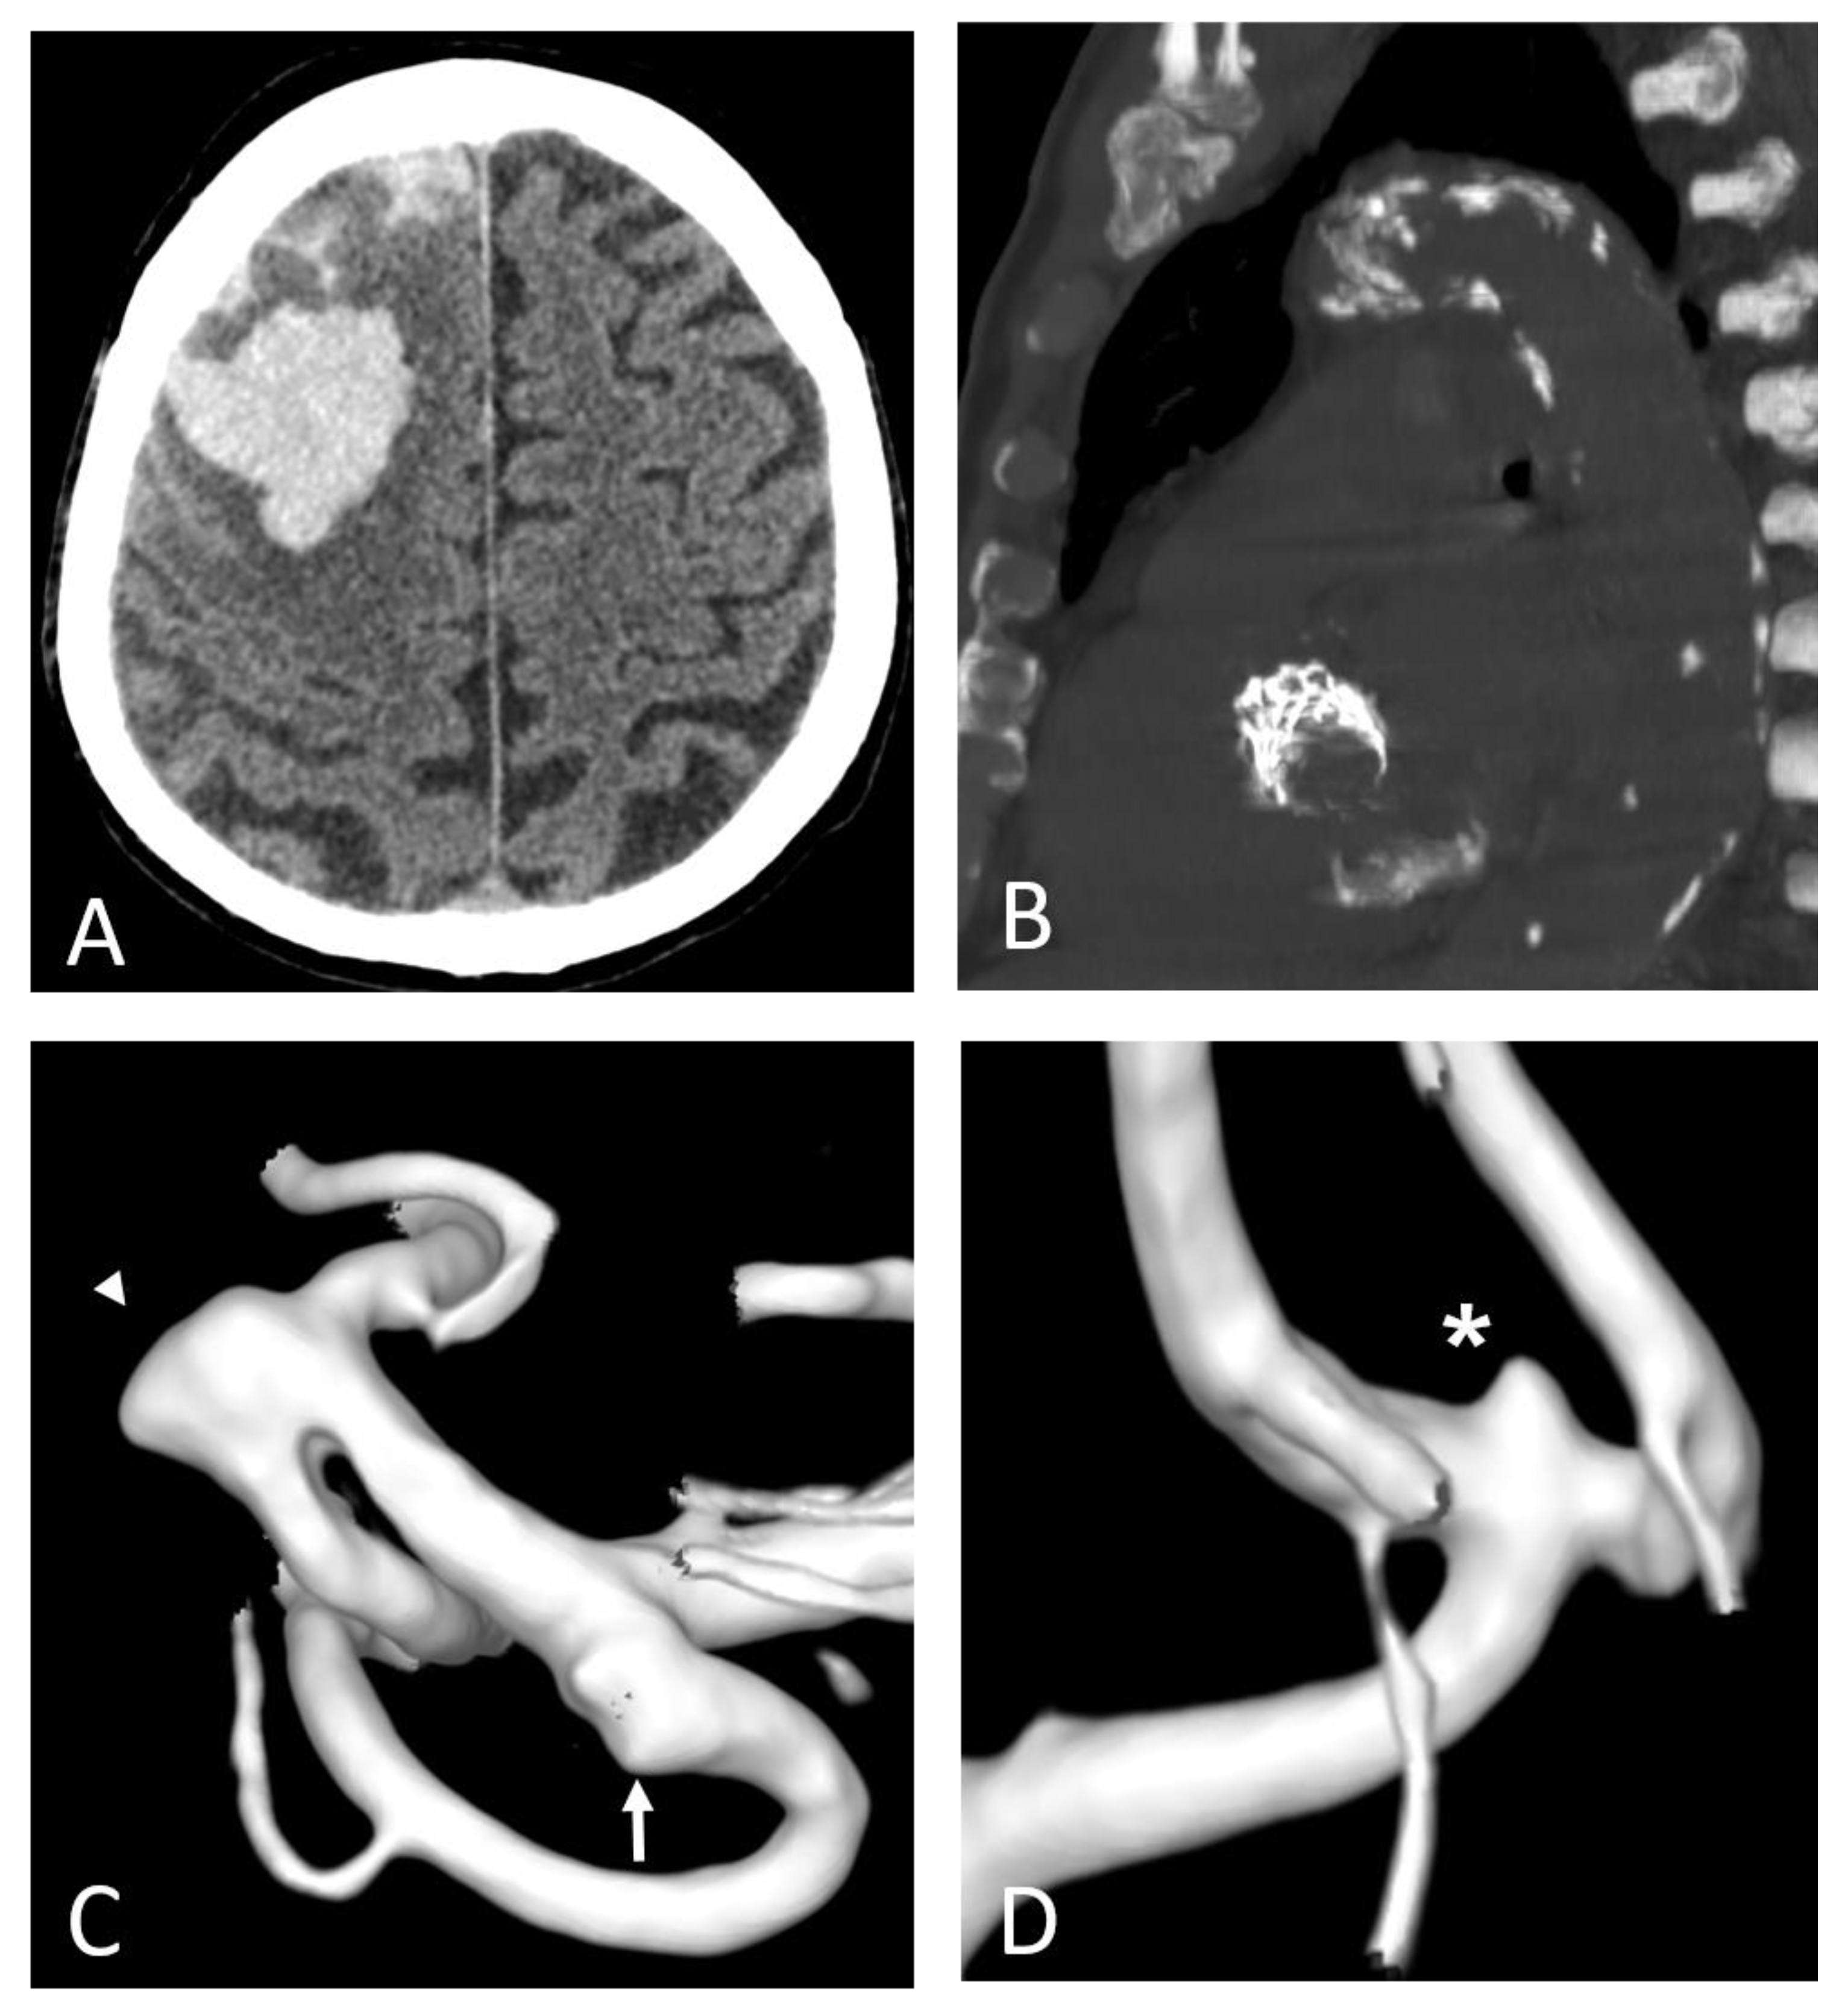

- Signorelli, F.; Sela, S.; Gesualdo, L.; Chevrel, S.; Tollet, F.; Pailler-Mattei, C.; Tacconi, L.; Turjman, F.; Vacca, A.; Schul, D.B. Hemodynamic Stress, Inflammation, and Intracranial Aneurysm Development and Rupture: A Systematic Review. World Neurosurg. 2018, 115, 234–244. [Google Scholar] [CrossRef] [PubMed]

- Hosaka, K.; Hoh, B.L. Inflammation and Cerebral Aneurysms. Transl. Stroke Res. 2013, 5, 190–198. [Google Scholar] [CrossRef] [PubMed]